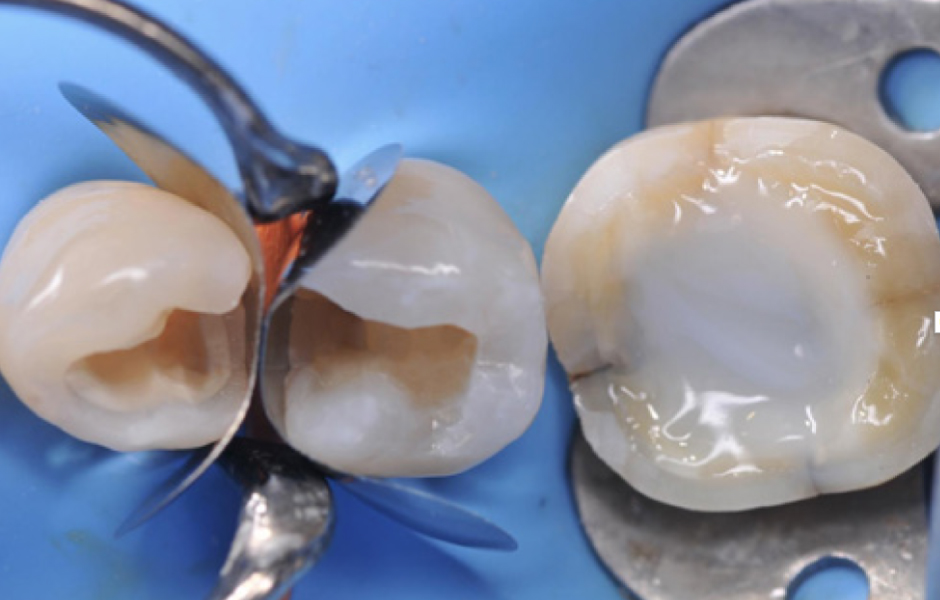

Obr. 3: Preparace kavit. Konečný stav preparací kavit: Byly dokončeny dvě kavity II. třídy a u prvního moláru byla provedena preparace pro overlay. Infrakce na meziální stěně moláru zůstala nedotčena; aby se zabránilo její další propagaci. Bude zpevněna při cementaci nepřímé rekonstrukce.

Obr. 4: Okamžité utěsnění dentinu. Obnažený dentin prvního moláru byl okamžitě ošetřen sealerem a byla provedena dostavba za použití SimpliShade Bulk Fill Flow (Kerr). Následně byly na premoláry umístěny dvě sekční matricové pásky pro postranní úsek, fixované oranžovým klínkem a kroužkem, pro zhotovení výplní II. třídy.